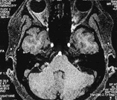

2.面部檢查:在做常規(guī)檢查前,患者可行初步自我檢查,如兩側(cè)眼睛是否對稱、皺眉時兩側(cè)幅度是否一致、抬眉時是否出現(xiàn)額部皺紋等;常規(guī)檢查以肌電圖及腦電圖檢查為常見,用電刺激患側(cè)眶上神經(jīng)時,同側(cè)眼輪匝肌及其他面神經(jīng)支配的肌肉出現(xiàn)同步收縮,這是本病的主要特點。正常者或其他面部疾病者進行此檢查時,僅引起患側(cè)眼輪匝肌的收縮;為排除乳突及顱骨病變,應(yīng)進行乳突及顱骨X線攝片、頭顱CT及MRI,以進行終確診。

面肌痙攣疾病的成功治療,首先是有高場強磁共振技術(shù)支持,使壓迫神經(jīng)的微血管在磁共振上一覽無余。